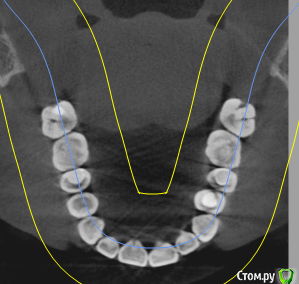

Добрый день! Два месяца назад началась моя история с зубами. Беспокоили дикие боли в зубах, как при пульпите, в 4-ке и 5-ке. Сделано было несколько прицельных и рентгеновских снимков, которые ничего не показали. Обошла пять стоматологов, никто проблем не находил, отправляли к лору или неврологу. КТ никто сделать не предложил, к сожалению. Было принято решение совместно с шестым! стоматологом депульпировать эти два зуба. При удалении нервов стоматолог сказал, что нервов уже почти нет и в 4, и в 5, сказал, что у меня хронический периодонтит, а в 4-ке стоматолог увидела на снимке (когда проверяла каналы после лечения) наружную резорбцию корня. В 5-ку поставили сразу постоянную пломбу, в 4-ке сейчас стоит временная (материал МТА). Но боль в 4-ке осталась, она не такая конечно сильная, как была, но ноющая, усиливается после горячего, после еды, в основном. И над зубом есть свищ, он не беспокоит и не болит при надавливании (стоматолог говорит, что это материал под десной, из-за резорбции) Врач говорит, что все пройдет, и через 2 месяца ставим постоянную пломбу, но болит уже месяц. Я сама сделала КТ, очень прошу вас посмотреть и подсказать, как действовать дальше? Может проще удалить этот зуб и поставить имплантат?